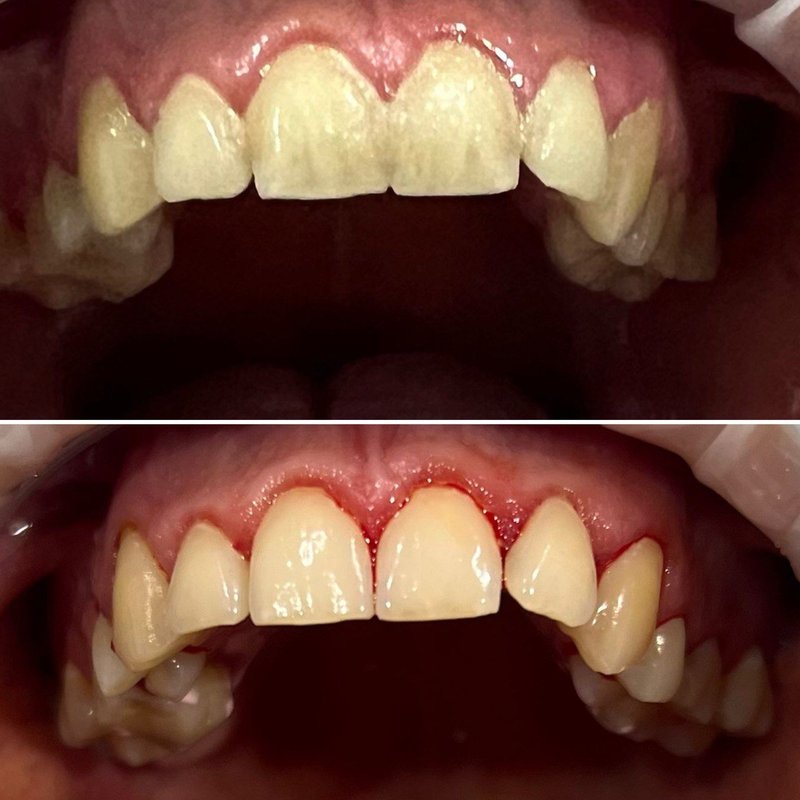

Фотогалерея